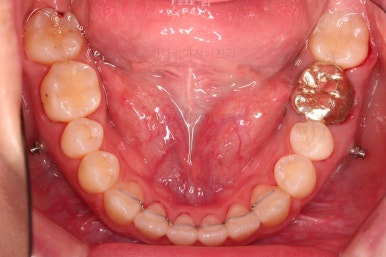

부산치아교정잘하는곳 키다리아저씨치과에서 치료를 종료했을 때의 사진입니다.

위아랫니가 가지런해졌고요.

다시 틀어지지 말라고 적절한 유지장치를 구성합니다.

보철 치아의 위치/크기로 인해 100% 중앙선은 맞기 힘드나 가장 잘 맞추어 놨고, 앞니의 각도도 매우 좋아졌습니다.

아래 앞니도 단순히 머리 부분만 뒤로 눕힌 것이 아니라 뿌리까지 뒤로 당겨왔고요.